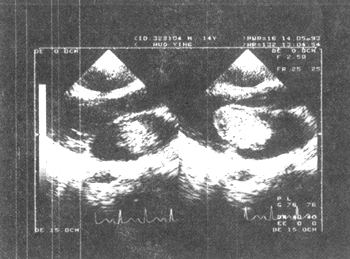

⑴左房粘液瘤(图1)明确诊断依据:①左房内见到异常的点片状回声聚集成团。轮廓清晰,边缘较规整,大致为椭圆形、长椭圆形的团状回声,其内部回声强度较均匀,基底部在房间隔上。如蒂较大,可显示蒂的部位及大小(如胸骨左缘左室长轴图,左右室流入道长轴图,心尖部四心腔图,大动脉短轴图)。②肿瘤的团状回声随心动周期活动于左房、左室之间。收缩期全部瘤体均能回到左房腔内,舒张期均达到二尖瓣或通过二尖瓣口进入左室。其在左房左室内位置随着其蒂的附着部位及肿瘤的体积大小和形态而不同(胸骨左缘左室长轴图,左右室流入道长轴图,心尖四心腔图)。③左室二尖瓣水平短轴上,可见收缩期肿瘤回声在二尖瓣之后,与二尖瓣可分开,回缩至左房。舒张期肿瘤随血流移动,经过二尖瓣口脱入左室,圆形的二尖瓣口可被肿瘤回声充满。

收缩期 舒张期

图1 左房粘液瘤超声心动图(左心长轴)